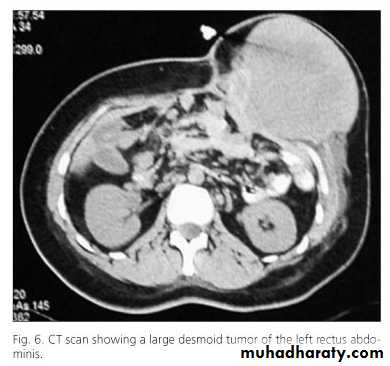

Desmoid tumor

This is usually considered by pathologists to be a hamartoma or a fibroma due to repeated trauma.Is more common in women.

Histologically they contain plasmoidal cell masses resembling giant cells. They undergo central myxomatous change.

Surgical excision with a wide margin is required to prevent recurrence which is a frequent problem.